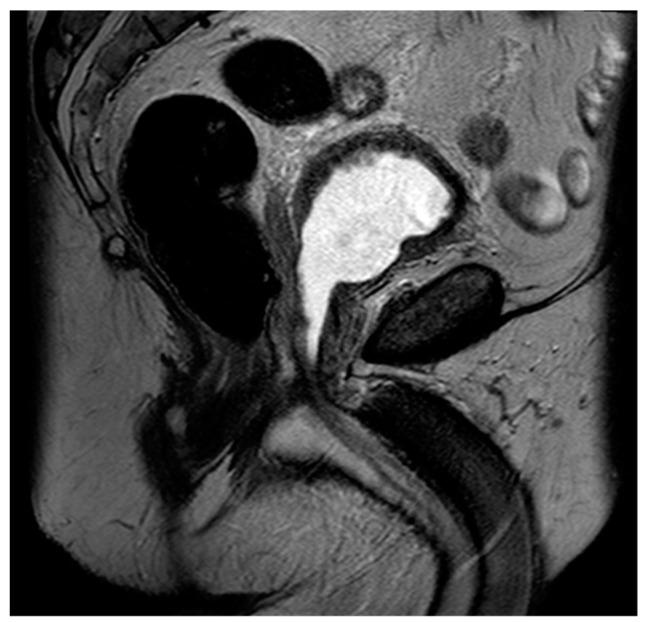

Contemporary Review of Multimodality Imaging of the Prostate Gland.

Tissue changes and the enlargement of the prostate, whether benign or malignant, are among the most common groups of diseases that affect men and can have significant impacts on length and quality of life. The prevalence of benign prostatic hyperplasia (BPH) increases significantly with age and affects nearly all men as they grow older. Other than skin cancers, prostate cancer is the most common cancer among men in the United States. Imaging is an essential component in the diagnosis and management of these conditions. Multiple modalities are available for prostate imaging, including several novel imaging modalities that have changed the landscape of prostate imaging in recent years. This review will cover the data relating to commonly used standard-of-care prostate imaging modalities, advances in newer technologies, and newer standards that impact prostate gland imaging.